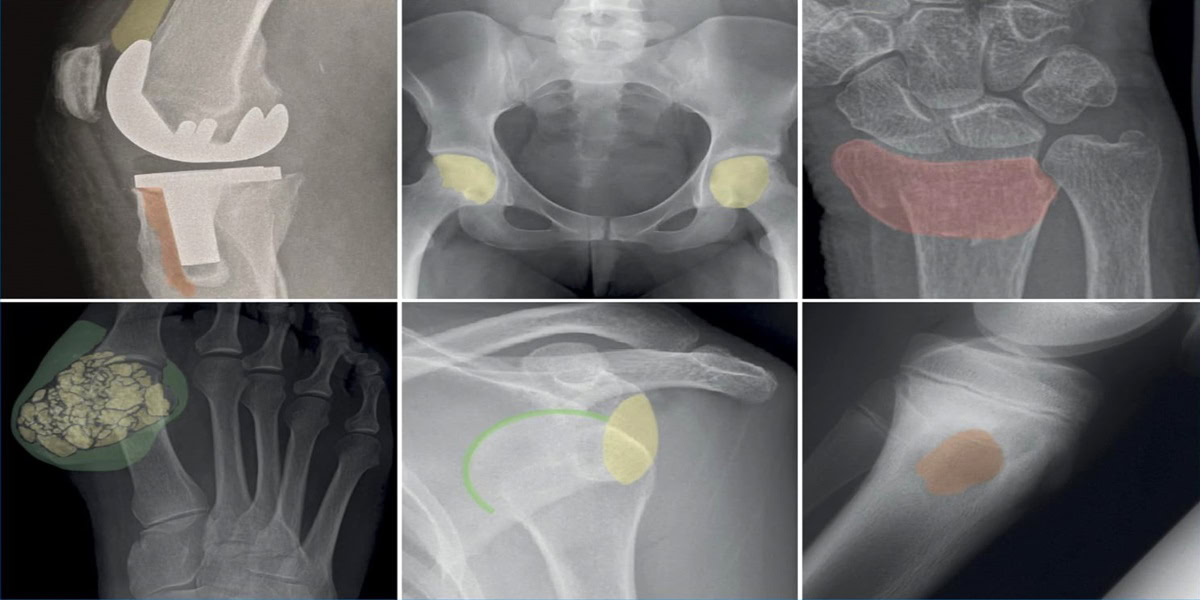

BỆNH LÝ XƯƠNG KHỚP

Danh từ thoái hóa khớp được giới thiệu lần đầu tiên vào năm 1886 bởi bác sĩ J.K.Spender. Đây là bệnh thường gặp nhất trong các bệnh lý xương khớp, liên quan chặt chẽ với tuổi và là nguyên nhân chính gây đau, mất khả năng vận động, giảm chất lượng cuộc sống ở người cao tuổi, gây tổn hại đến kinh tế gia đình người bệnh và tạo gánh nặng cho chi phí ý tế. Tổn thưởng cơ bản đầu tiên là sụn khớp, sau đó tổn thương xương dưới sụn, dây chằng, các cơ cạnh khớp và màng hoạt dịch…

Gãy xương đùi là một chấn thương phổ biến, đặc biệt là ở những người lớn tuổi. Gãy xương đùi ở người cao tuổi thường gây ra bởi té ngã tưởng như không nguy hiểm. Ở những bệnh nhân trẻ tuổi nguyên nhân thường gặp hơn của một chấn thương thường là do va đập mạnh như tai nạn xe hơi. Gãy xương đùi cũng có thể được gây ra bởi xương bị suy yếu từ khối u hoặc nhiễm trùng, hay còn gọi là gãy xương bệnh lý…

Chấn thương cột sống là tổn thương hệ thống đốt sống-đĩa đệm-dây chằng, có hậu quả nặng nề do các tổn thương thần kinh và biến chứng gây ra. Nguyên nhân: tai nạn giao thông 39%, sinh hoạt 25%, ngã cao 22%, tai nạn thể thao 7% và nguyên nhân khác 7%. Tổn thương phối hợp đa chấn thương trong 70% trường hợp…

Khớp vai là khớp quan trọng trong vận động. Khả năng chuyển động của khớp vai lớn hơn các khớp khác. Tuy nhiên, khớp vai không vững chắc so với các khớp khác do bề mặt của ổ chảo nhỏ và nông so với chỏm xương cánh tay. Khớp vai liên quan nhiều cấu trúc xương và phần mềm quanh khớp. Các thay đổi giải phẫu hay bệnh lý các cấu trúc này ảnh hưởng vận động khớp…